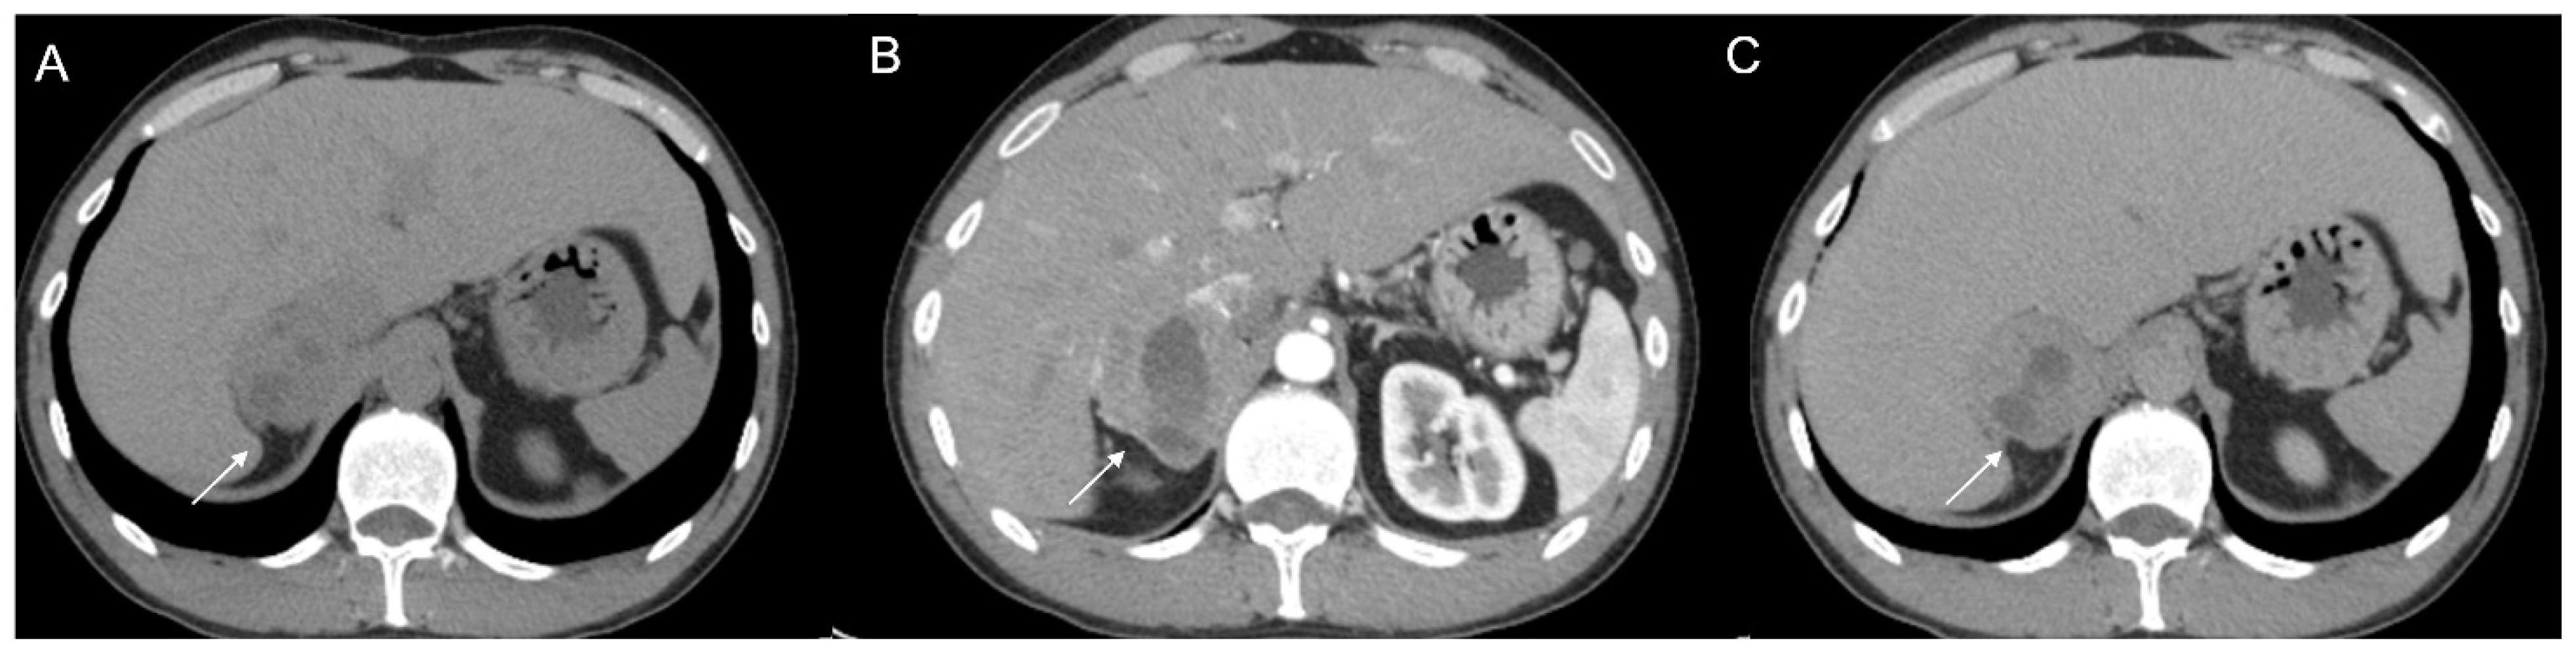

Figure 14.

Axial unenhanced (a), arterial (b), and coronal venous (c) CT phases show a lung carcinoid metastasis (arrow) of the left adrenal gland. Additional hypervascular metastasis can be seen in the liver, particularly in the arterial phase.

Figure 16.

(a) Axial and (b) coronal venous phases CT show an ACC of the left adrenal gland presenting as a large mass (arrow) of heterogeneous appearance with extensive neoplastic thrombosis of the ipsilateral renal vein.